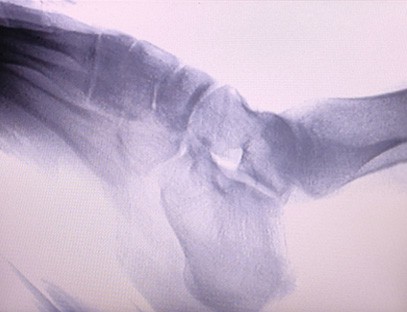

A X-ray of Extremities rendszer egy speciális radiográfiai rendszer, amelyet a végtagok csontjairól és ízületeiről készítenek, beleértve a karokat, lábakat, kezeket és lábfejeket. A rendszert úgy tervezték, hogy tiszta és pontos képet adjon a végtagok csontjairól és ízületeiről diagnosztikai célokra. A berendezés sokoldalú, könnyen használható, és számos ortopédiai és sportorvosi állapot diagnosztizálására használható.

1. Ortopédia: A rendszer ideális mozgásszervi betegségek, például törések, ízületi gyulladások vagy diszlokációk diagnosztizálására. Legjobban a végtagcsontok zárt redukciójára, rögzítésére, tűbefűzésére és idegentest eltávolítására fejti ki hatását, különösen akkor, ha egymásba illeszkedő intramedulláris szeg vagy rögzített támasz beépítésével együtt alkalmazzák.

2. Sportgyógyászat: A berendezés használható az ízületi mobilitás, a csont- és szalagkárosodás mértékének, vagy az idegen tárgyak, például szilánkok elhelyezkedésének felmérésére.Sérültek kezelése sportpályákon, épületekben, óceánjáró hajókon, távoli területek és katonai terephelyek.